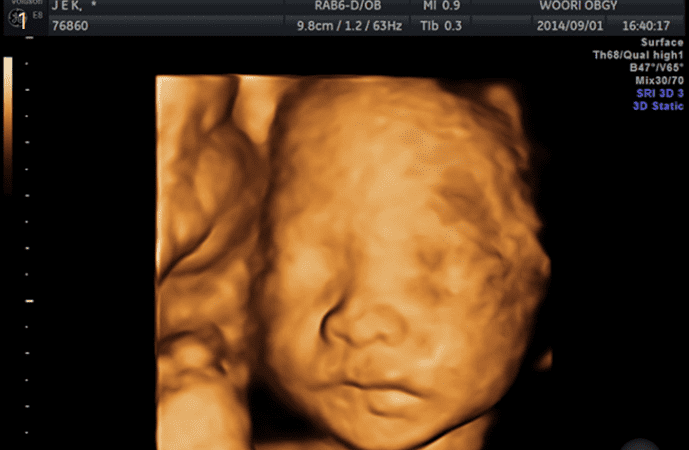

4D 입체영상초음파

입체영상초음파는 선택검사이며, 예약이 필요합니다. 태아의 얼굴, 손, 발, 척추 등이 가장 잘 보이는 임신 23-28주 사이에 실시하여 실물과 유사한 사진을 얻어 미리 아가를 만나볼 수 있는 검사입니다. 우리산부인과는 보다 감각 있는 사진을 위하여 초음파 "GE HD live "을 사용하고 있습니다.